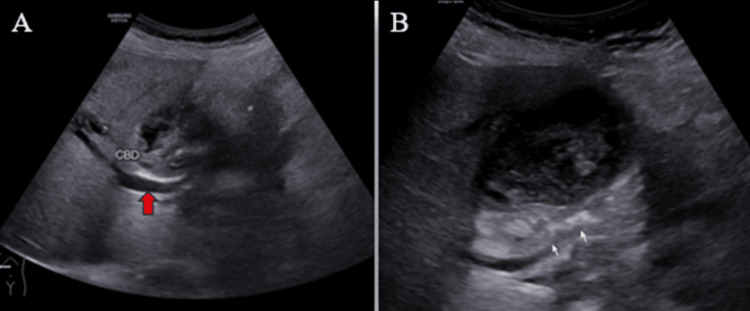

Ultrasound (US) examination revealed bilobar intrahepatic biliary radicle (IHBR) dilatation (Figure 1), and the gallbladder appeared overdistended with large, heterogeneously hypoechoic content devoid of vascularity on color Doppler (Figure 2). The gallbladder wall appeared thickened, measuringapproximately 4 mm. Furthermore, the proximal CBD appeared mildly dilated, measuring 8 mm, with a heterogeneously hypoechoic lesion within the midportion causing its narrowing (Figure 3). Multiple subcentimetric to enlarged necrotic lymph nodes were also observed in the porta-hepatis, periportal, and retroperitoneal regions (Figure 4).

These findings were suggestive of an infective etiology, likely indicative of acute cholecystitis with thick purulent content in the gallbladder and a mass lesion in the mid-portion of the CBD.